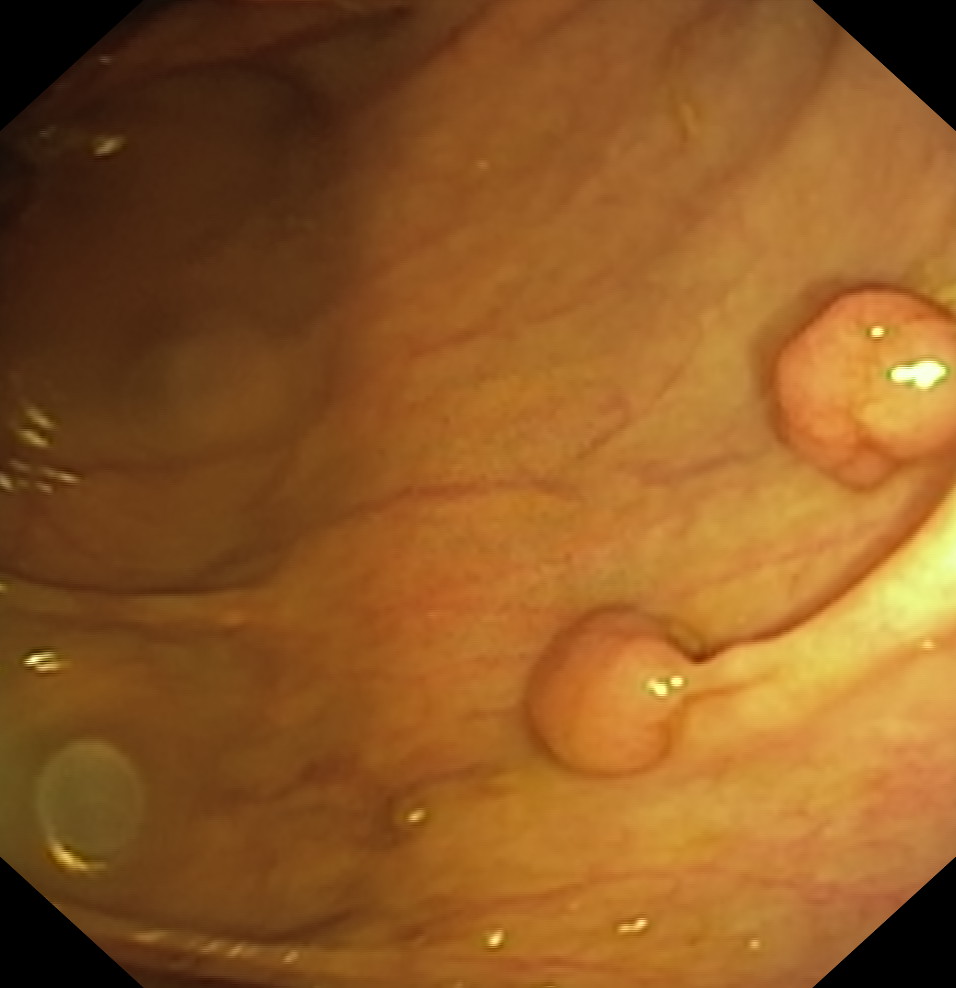

Polipy